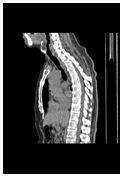

身体の形態も

病変も一目瞭然

身体の形態ははっきり

見えているが病変が不明